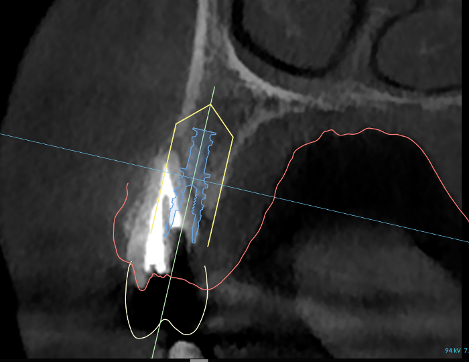

During your initial consultation at Arcadia Perio, Dr. Peterson will review your medical history, perform an oral exam, take digital X-rays, and likely consult your general dentist. Sometimes, a 3D scan is taken with our cone-beam computed tomography scanner to accurately visualize your unique anatomy and plan virtual implant treatment. The initial planning phase is as thorough as possible to optimize long-term success and determine your optimal solution.

The 3D image we took during your consultation is used to create computer-aided guidance with our sophisticated X-Nav system. Visualizing the placement of your dental implants in 3D eliminates guesswork and potential complications. In the skilled hands of Dr. Peterson, proper planning combined with X-Guide Dynamic 3D Navigation during surgery elevates surgical excellence while increasing efficiency and safety. If you received full-mouth dental implants, our customized, streamlined protocol enables Dr. Peterson to fit you with temporary 3D-printed teeth within 24 hours of your surgical procedure.

3D planning

CBCT & planning

Planning detail